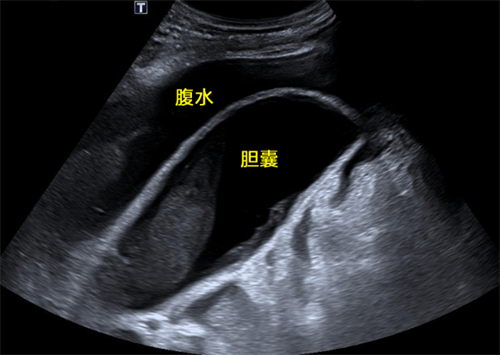

(术前超声胆囊大小12.4×5.2cm,张力较高,周围可见大量腹水)

(肝周积液明显减少,引流管经过胆囊床处唯一可用的狭窄的肝脏置入胆囊腔内,引流通畅,胆囊张力明显减小)